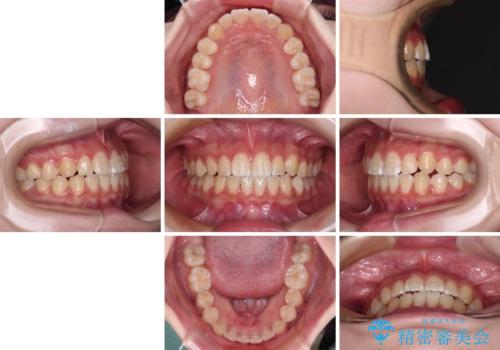

- 前歯のデコボコと磨きにくい奥歯を気にして来院された患者様です。

左右ともに上顎第二大臼歯が外側に転位しており、大変磨きにくくなっているため、補助装置により内側に引き込むことで改善することとしました。

外側を向いていた奥歯は比較的早い時期に歯列に収まり、咬み合わせも磨きやすさも改善することができました。

歯列は元々悪くなかったので、1年ほどで治療を終えることができました。